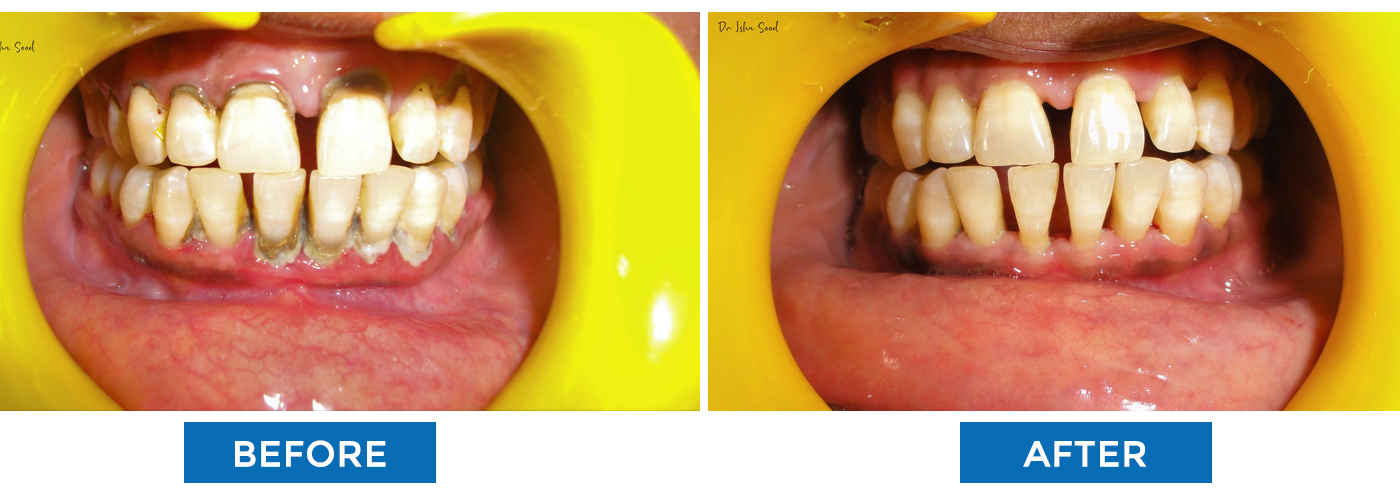

Teeth Cleaning (Scaling)